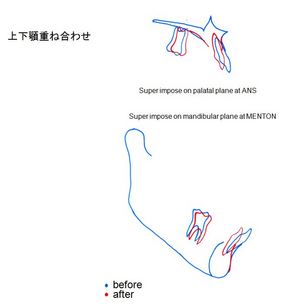

終了時重ね合わせ評価①

終了時重ね合わせ評価②